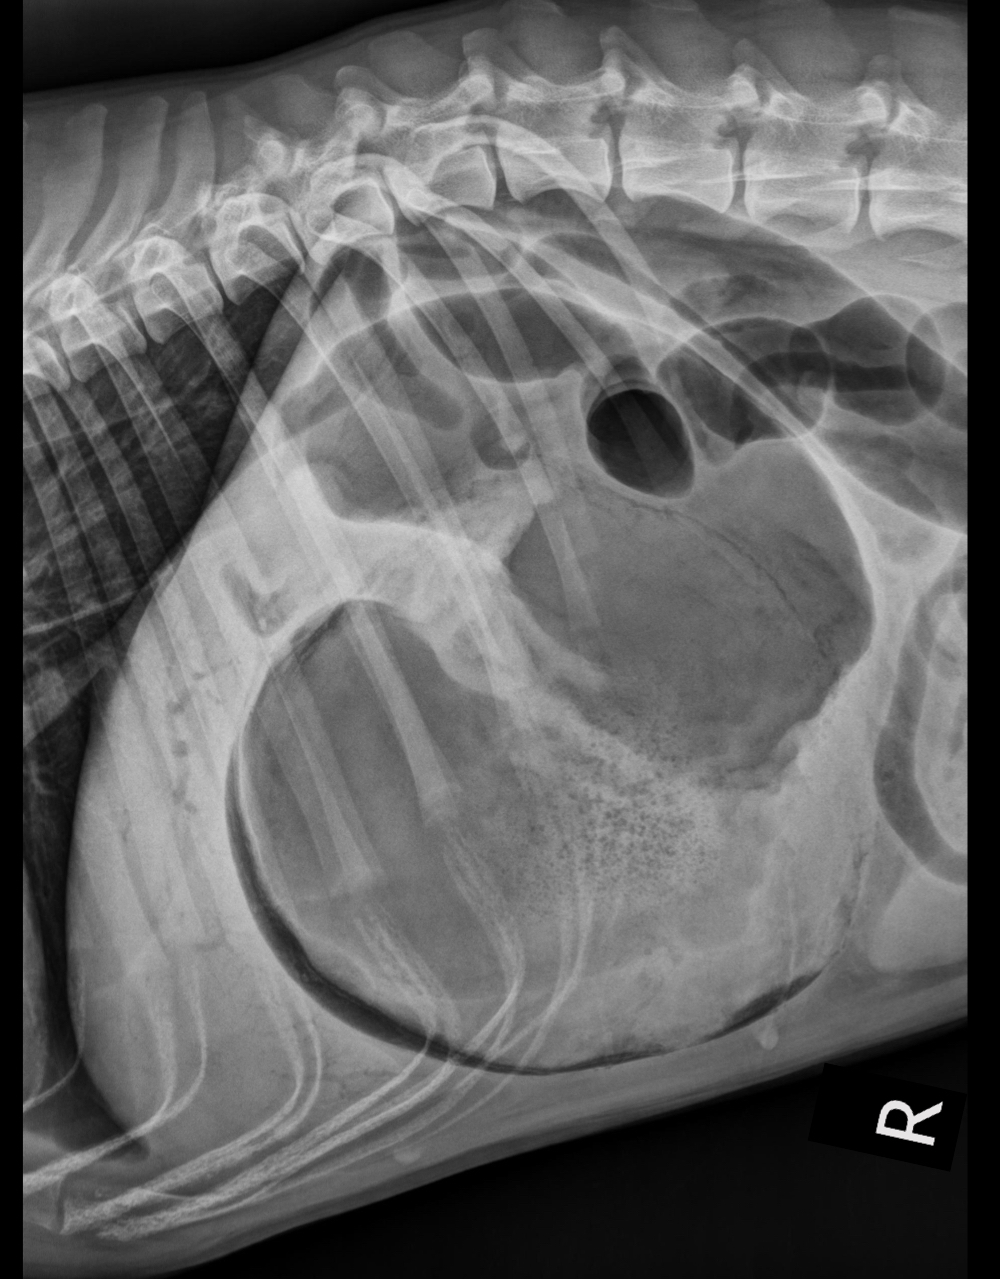

What is occurring in this radiograph?

A

• left crura is cranial on a right lateral projection

• gas and mineral opacity indicative of ingesta = herniated intestine in thorax!

(secondary to diaphragmatic rupture)